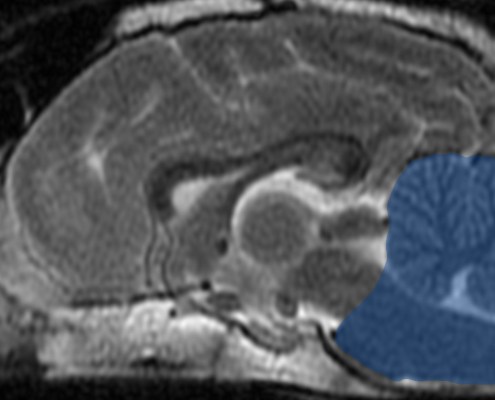

Case: French Bulldog with head tilt & ataxia

Left head tilt, ataxia, and previous history of optic neuritis

2yr MC Golden with acute onset of circling, leaning to the left, and lethargy